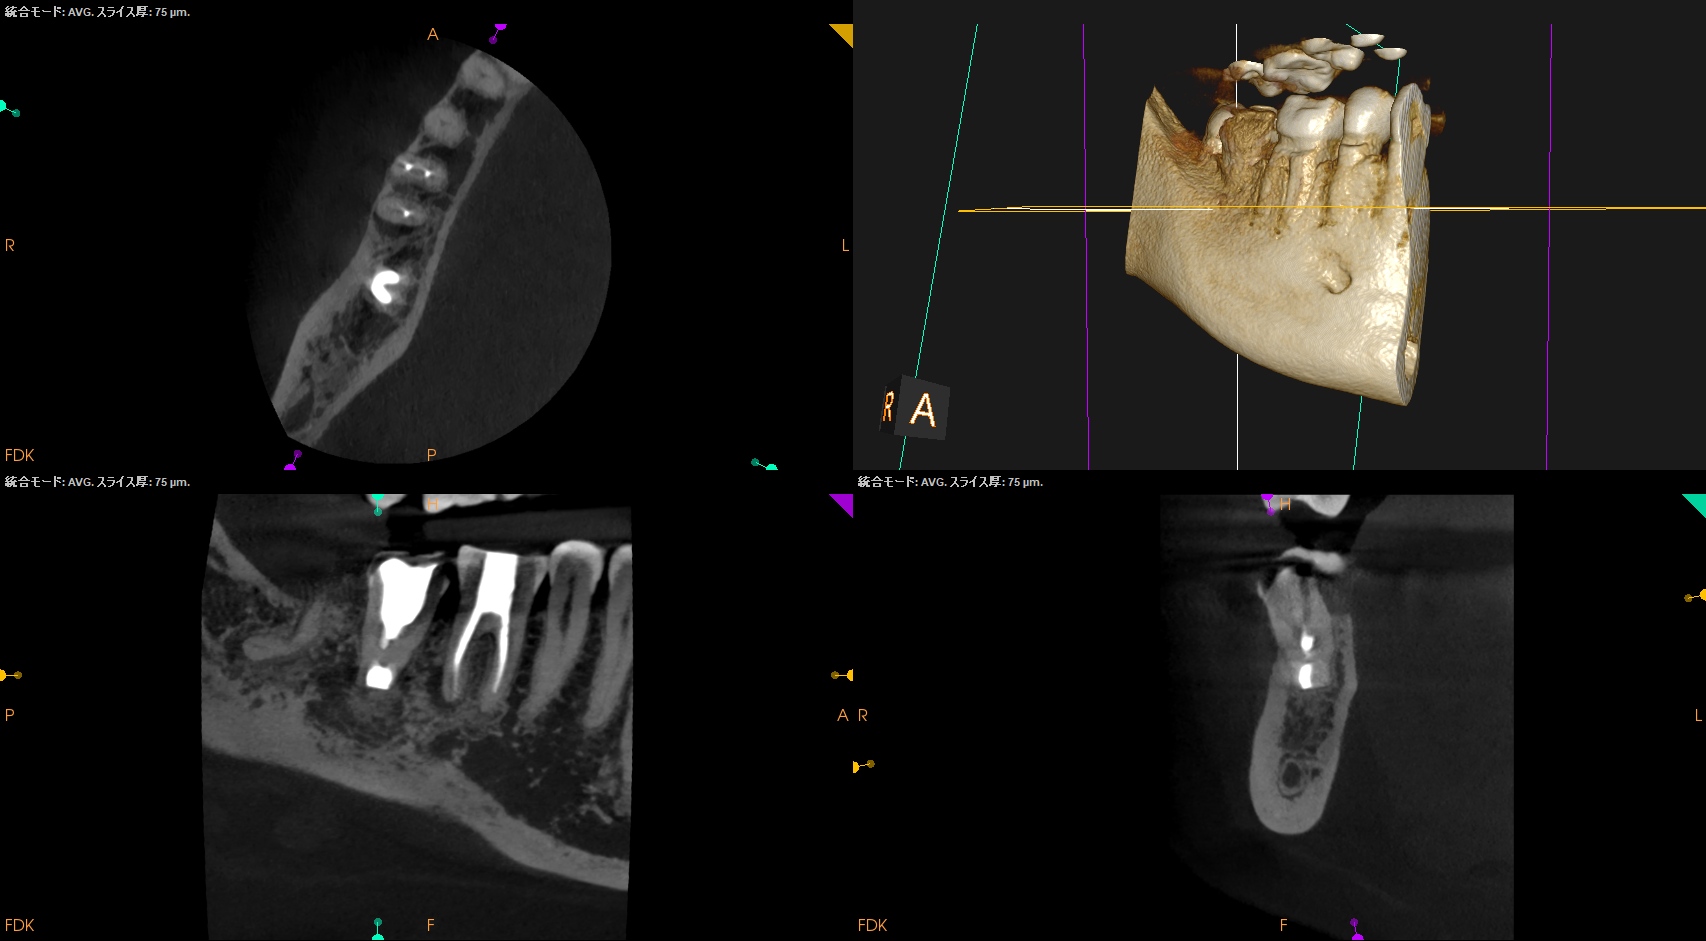

#31 Intentional Replantation 1yr recall(2025.11.28)

ML

MB

D

初診時と比較した。

劇的に治癒していることがわかる。

打診検査時のアンキローシス音もないことから、この日で終診とさせていただいた。